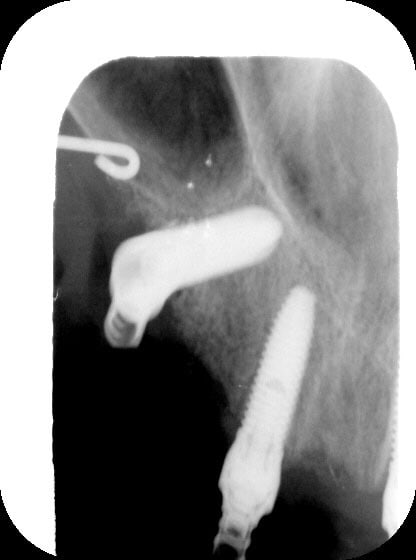

Ci-joint qq images de mon dernier petit All-on-"FOUR" qui date de la semaine dernière.

P1000812 gqllw9 - Eugenol

P1000663 t3yc0w - Eugenol

P1000816 mchm9u - Eugenol

009 fx01gm - Eugenol

024 vownvo - Eugenol